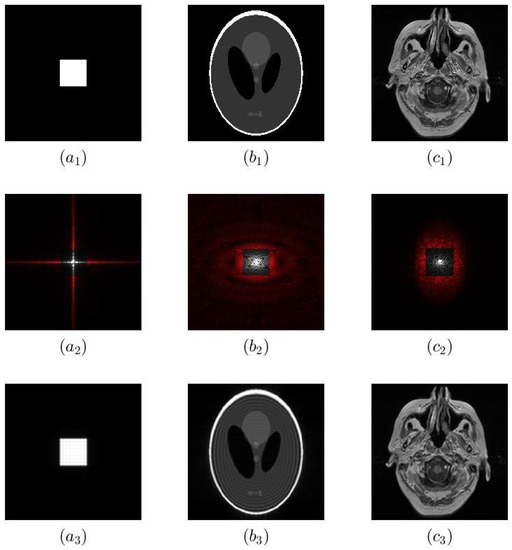

In this Section, we introduce the three test images, depicted in Figure 1. These range from the minimalist rectangle function, which provides a discontinuity and little else to confound analysis, to an example slice of an MRI for a more realistic test. This variety of test images makes our analysis more robust.

The first test image is a 400 × 400 image of a 2D rectangle function shown in Figure 1( a 1 ). The central 200 × 200 pixels have value 1 and the remaining pixels are zeros. One of the advantages of this test image is that its Fourier transform can easily be calculated mathematically: it is a 2D sinc function. This means that we know the space and Fourier domain samples exactly, as opposed to other examples where we know only one domain exactly and must determine the other numerically at the cost of aliasing.

G ( u , v ) was sampled with 400 × 400 sampling points up to a cutoff frequency of 10,000 lines/mm in both x and y. The spectrum is truncated (in Figure 1( a 2 ), truncation of 80% of Fourier coefficients is shown) and inverse Fourier transformed. The resulting image (Figure 1( a 3 )) exhibits Gibbs ringing and can be compared with g ( x , y ) sampled at 20,000 lines/mm.

The second test image is shown in Figure 1( b 1 ) is a 400 × 400 Shepp–Logan phantom. It was developed as a test image for MRI reconstruction algorithms, resembling an MRI head section, and is a widely used test image in Gibbs ringing reduction studies in MRI [6,9,14]. The Fourier coefficients can be approximated by discrete Fourier transform of the phantom. We know the ground truth in the space domain, but do not know the Fourier domain samples exactly.

Finally, the third test image is a 512 × 512 pixel MRI slice obtained from the Brain Tumor Progression dataset [21] of The Cancer Imaging Archive [22]. We will refer to this as MR image. It is shown in Figure 1( c 1 ). As before, we can use a discrete Fourier transform of the image to estimate the Fourier coefficients but, as with the Shepp–Logan phantom, we have a reduced reference. There is a small difference: the phantom is defined in the space domain, whereas the MR image was reconstructed from Fourier samples in the first place.

These three test images have increasing complexity: the rectangle function is a highly simplified test image; the phantom has edges that are not aligned with the x or y axis, which are not straight and which overlap; and the MRI is a real image with intricate details which lacks such clearly defined edges. We also have different knowledge about the ground truth of each image.

For all three images, we introduce ringing the same way. In the plots up to Figure 7, the central 20% of Fourier data remained on both the x and y axis. The magnitude of the Fourier data is shown in Figure 1( a 2 c 2 ). Fourier coefficients that are highlighted in red are set to zero. Adjusting the fraction of coefficients which are set to zero allows us to control the amount of ringing but maintain the number of samples to simplify comparisons. Figure 1( a 3 c 3 ) show the Fourier reconstruction based on the Fourier coefficients after truncation in the Fourier domain. There is visible ringing showing around the edges in all three images.

Figure 1. The three test images before and after introducing ringing. ( a 1 ) Original 400 × 400 numerically simulated square. ( b 1 ) Original 400 × 400 Shepp–Logan phantom. ( c 1 ) Original 512 × 512 MR image. ( a 2 c 2 ) Spectra of ( a 1 c 1 ). Fourier coefficients highlighted in red are set to zero, simulating zero padding of a reduced number of measured Fourier coefficients. ( a 3 c 3 ) Fourier reconstruction using ( a 2 c 2 ) showing visible ringing.